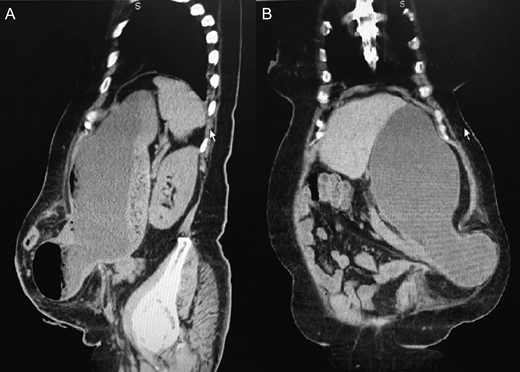

An abdominal computed tomography (CT) demonstrated a voluminous PH with part of the stomach protruded through the PH (Fig. 2A and B).

(A) Sagital view of the PH containing the distal part of the stomach. (B) Coronal view of the PH with gastric content in inferior left side of the abdomen.